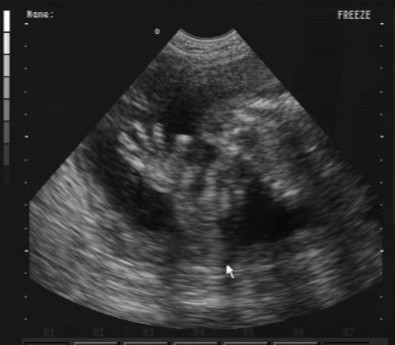

Sajnos nem bírtam ki a 30.-adik hétig,látni akartam Tomi babát azonnal.A genesisben voltunk,majdnem 3/4 órát moziztunk,azt mondták nagy baba,hát nem kizárt,az apja 193cm.

Liuska: Tomika gyönyörűséges! Az a kis nózi! El is hiszem, hogy nem bírtad ki a 30.hétig, én is kérdeztem a dokimat, hogyha meglesz végre valahára a 4D majdnem a 26.héten, ás 32 hetesen megyek a következőUH-ra kb, közte lehet-e egyet mozizni? :oops: Mosolygott, hogy persze, mondjuk hetente nem lenne értelme, de az belefér, hogy a 29.hét környékén... Asszem, bejelentkezem :D

Tegnap voltam dokinál. Méhszáj zárt. :)

Kicsit több a magzatvíz. Gyönyörű a kisfiam. Amikor mocorog, a pici feje dudorodik ki.

Még mindig harántfekvésben, bár folyamatosan tekergett az uh alatt. :)

Hanna: nekem személy szerint azt mondta az UH-s dokinénim, hogy a 25-26.hét körül a legjobban láthatóak, ilyenkor készülnek a legjobb képek. Persze, nem tudom, nulla a tapasztalatom. De hétfőn meglessük a dokinál 4D-ben Martint, majd hozok képet, meg a többiekén is lehet látni, hogy szinte napról napra husisodnak :lol: